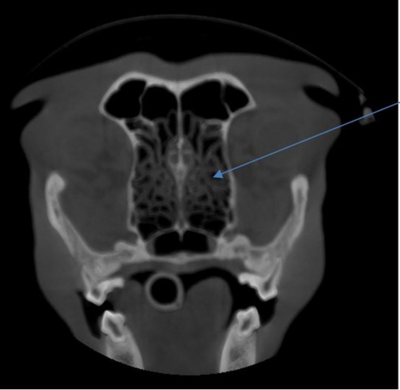

CT of a dog’s head with motion artefact. You can see double edges on the nasal turbinates (arrow).